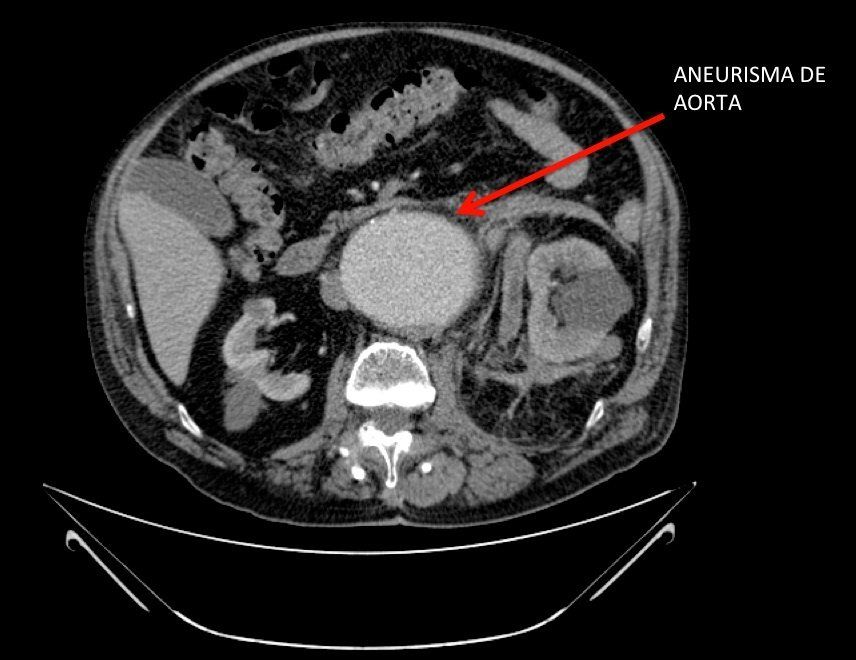

La localización más frecuente es la aorta abdominal (se les denomina triple A, o AAA, Aneurisma de Aorta Abdominal), es decir, por debajo de los riñones, y suele ser asintomático. De manera que su riesgo más temido es la rotura, situación que supone una elevada mortalidad. De ahí la importancia de detectarlo cuanto antes. Es muy habitual que se diagnostique cuando el paciente se somete a una ecografía, TAC o Resonancia por otro motivo; es decir, es un hallazgo casual. Nosotros recomendamos que en pacientes de riesgo, es decir, sobre todo varones, de más de 50 años, sobre todo si son hipertensos y/o fumadores, se hagan de vez en cuando un Ecodoppler aórtico por un Cirujano vascular. Es un prueba muy sencilla no agresiva, ideal para un primer despistaje. Mayor hincapié hacemos en los pacientes con antecedentes familiares de AAA; puede existir cierta tendencia hereditaria.

En la decisión influyen muchas circunstancias personales; la más importante de todas es si existe alguna sospecha de que el aneurisma haya producido algún síntoma como dolor. Pero en general, como norma básica, se aconseja tratar el Aneurisma de Aorta Abdominal cuando sobrepasa los 5,5 cm de diámetro. Si bien, como decía, pueden haber situaciones que obliguen a operarlos más pequeños, o esperar a que crezcan algo más. El profesional preparado para evaluar y tratar el aneurisma es el Especialista en Angiología y Cirugía Vascular; desconfíe de otras disciplinas.